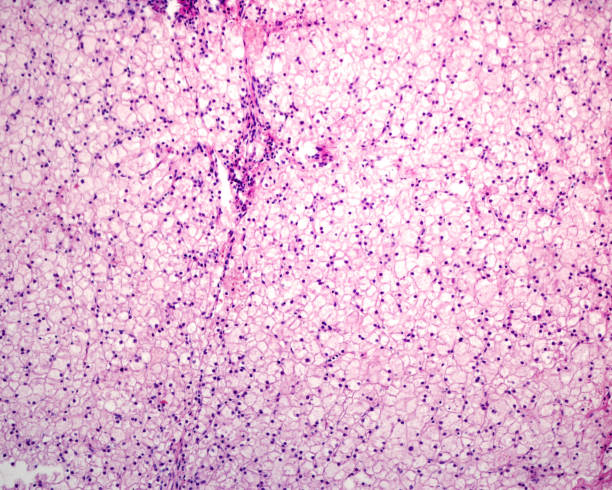

Der Glykogenkörper (Corpus gelatinosum) ist eine Sonderbildung im Bereich des Rückenmarks bei Vögeln. Die gallertige, eiförmige Masse ist eine Ansammlung glykogenreicher Zellen um den Zentralkanal im Bereich der Lendenschwellung (Intumescentia lumbosacralis) des Rückenmarks. Sie reicht rückenwärts bis an die Rückenmarkshäute. Zudem enthält der Glykogenkörper saures Gliafaserprotein und ist vermutlich ein Abkömmling der Astroglia. Die Funktion des Glykogenkörpers ist unbekannt, er ist kein Speicherorgan für Glykogen. Studien zur Enzymausstattung lassen vermuten, dass das Glykogen über den oxidativen Pentosephosphatweg verwertet wird und der Glykogenkörper bei Vogelembryonen bei der Lipid- und Myelin-Synthese im Zentralnervensystem eine Rolle spielt.

Der Glykogenkörper ist ein natürliches Hindernis bei der Myelografie.